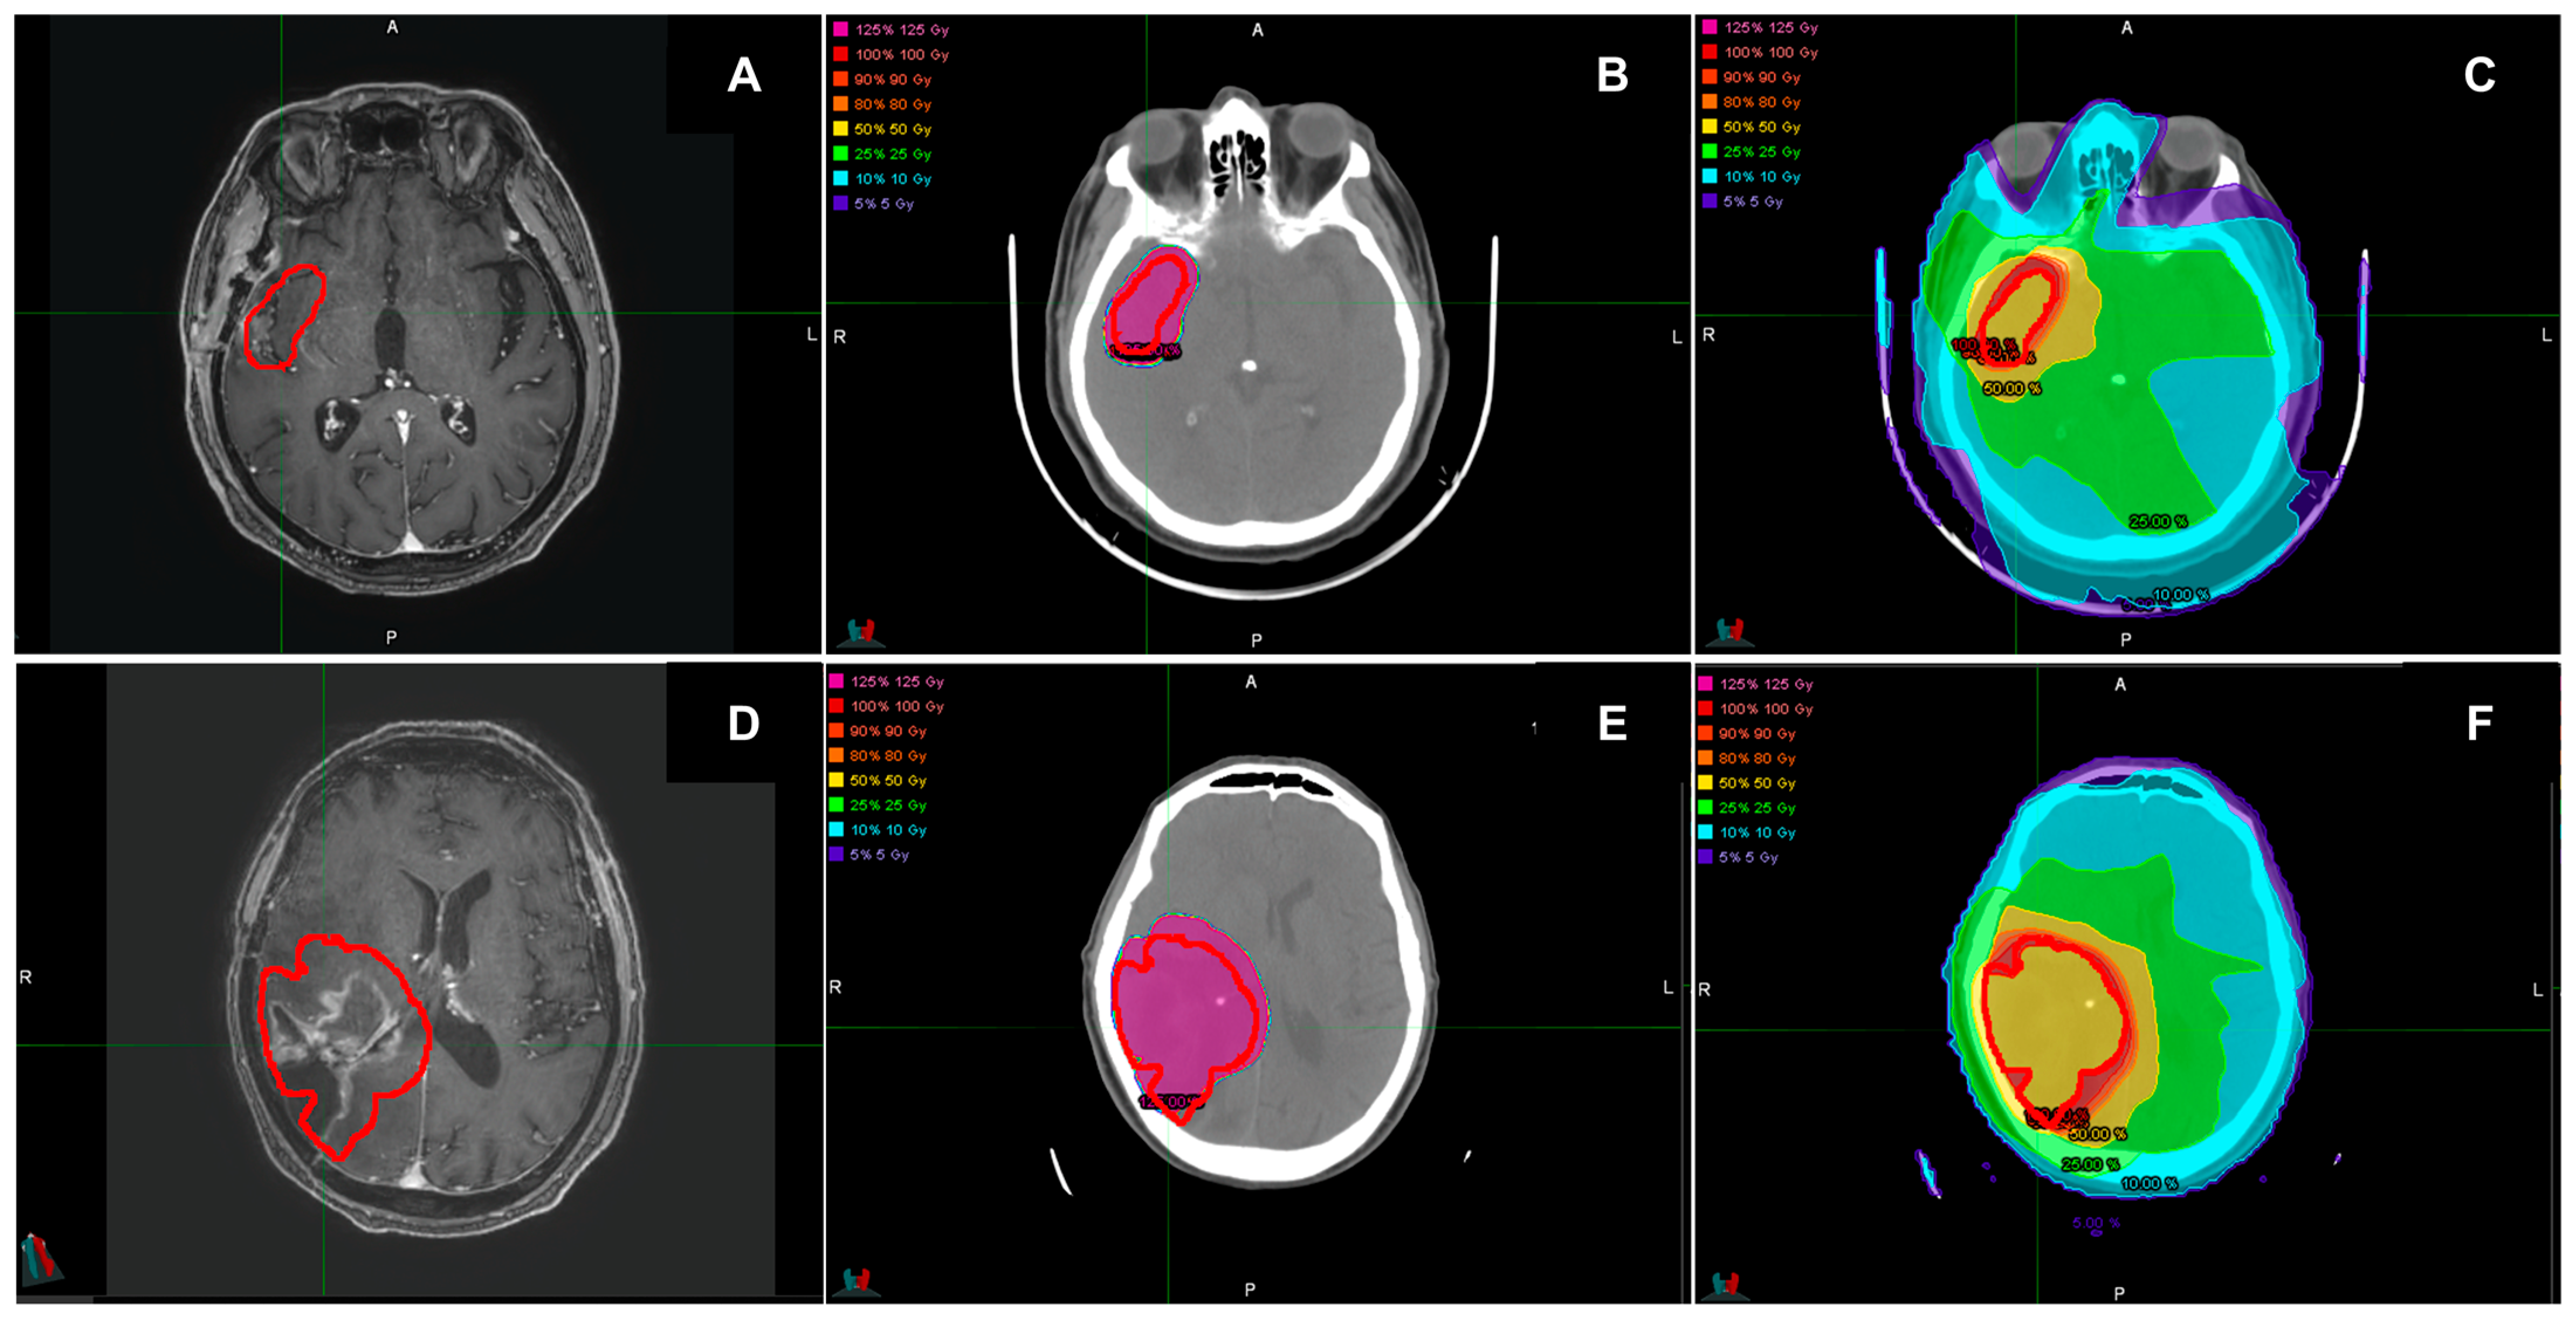

2.1. MRI and Target Delineation

2.2. Treatment Planning

2.3. Dose Calculation with 90Y-Labeled PVA-MBs

2.4. Dose Calculation with VMAT